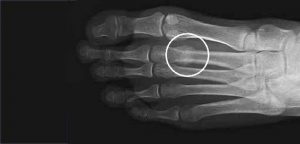

Son fracturas que ocurren generalmente en los pies, producen dolor crónico localizado en un punto, alivian en reposo, aumenta el dolor al caminar o apoyar la zona afectada.

Las fracturas por estrés pueden ocurrir en huesos sometidos a presión constante y repetida, por sobreuso, o micro traumatismos repetidos. Pueden ocurrir en los pies, la rodilla, tibia, peroné, cuello femoral, vértebras, antebrazos etc.

Se puede sospechar el diagnóstico al examinar al paciente y escuchar su historia clínica, Las Rx en algunas ocasiones pueden mostrar la lesión, pero generalmente pasan desapercibidas en los primeros días de los síntomas. La RESONANCIA MAGNÉTICA es el exámen más preciso que puede revelar la lesión y confirmar el diagnóstico que se sospecha.